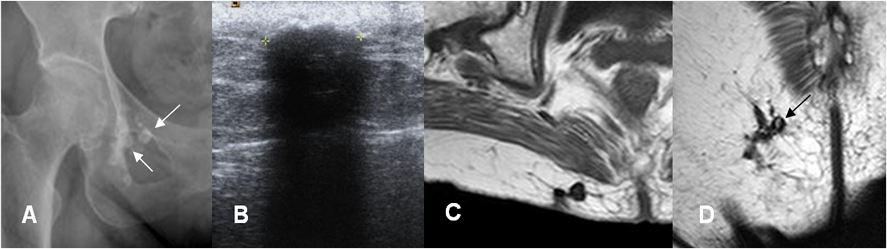

Fig 210B. Miositis osificante.

A: Rx de cadera y B: TAC axial. 2 casos diferentes donde existe calcificación de tejidos blandos en relación con grupos musculares, por miositis osificante.